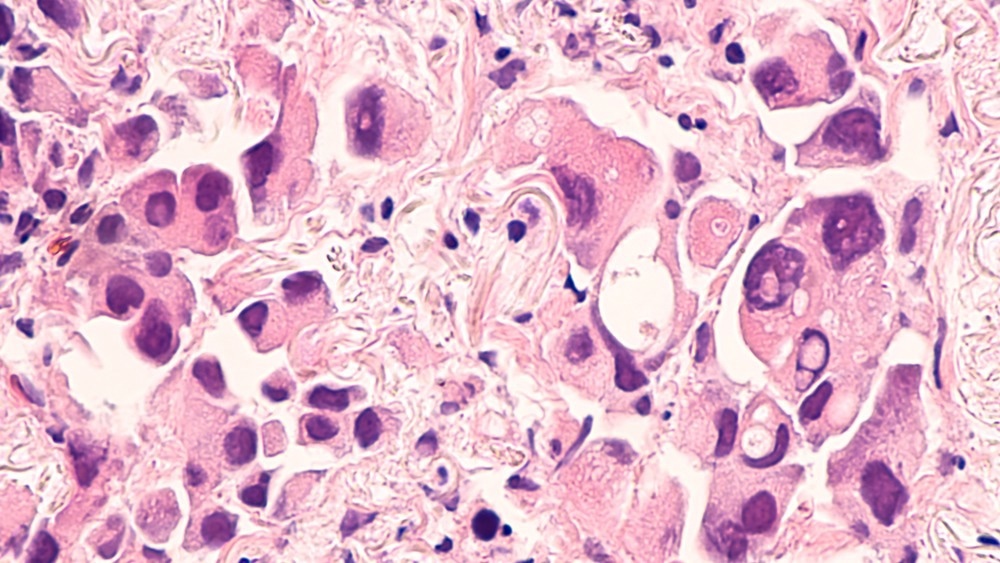

Image Credit: ShutterStock/David A Litman

One of the challenges, especially for early detection, is false positives. Even with an excellent assay to detect breast cancer, colon cancer, or prostate cancer, many people are still incorrectly diagnosed with prostate cancer due to this test, consequently causing a lot of avoidable grief.

Therefore, it is crucial that when we are using these new, fantastic ways to screen populations, we pair this with valuable and efficient ways to validate screenings. We want to find prostate cancers but do not want to misdiagnose a healthy person.